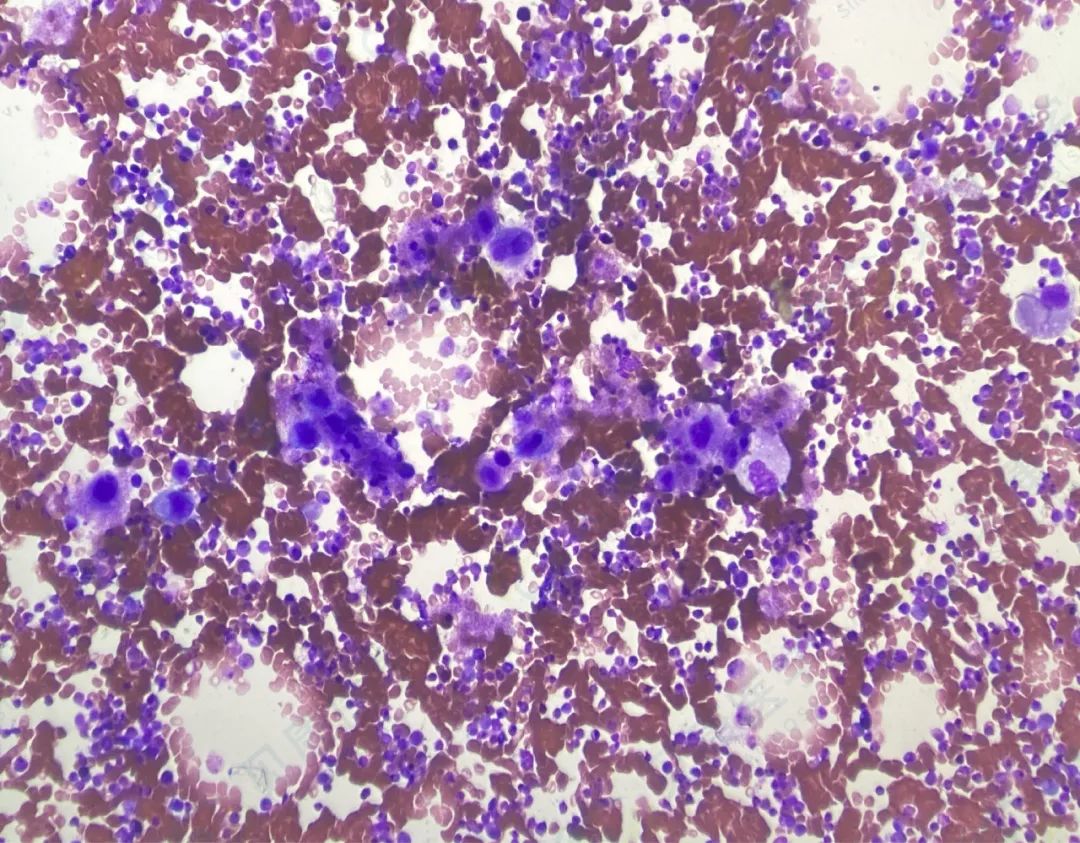

【形态学病例分享】第八十八期

患者基本信息:

女,49岁,发现血小板明显增多入院。

血常规:

WBC 14.12×

10

9

/L

RBC 4.01×

12

HB 124g/L

plt 2065×

细胞形态学

分子生物学

病理

诊断结果

慢性粒细胞白血病(慢性期)